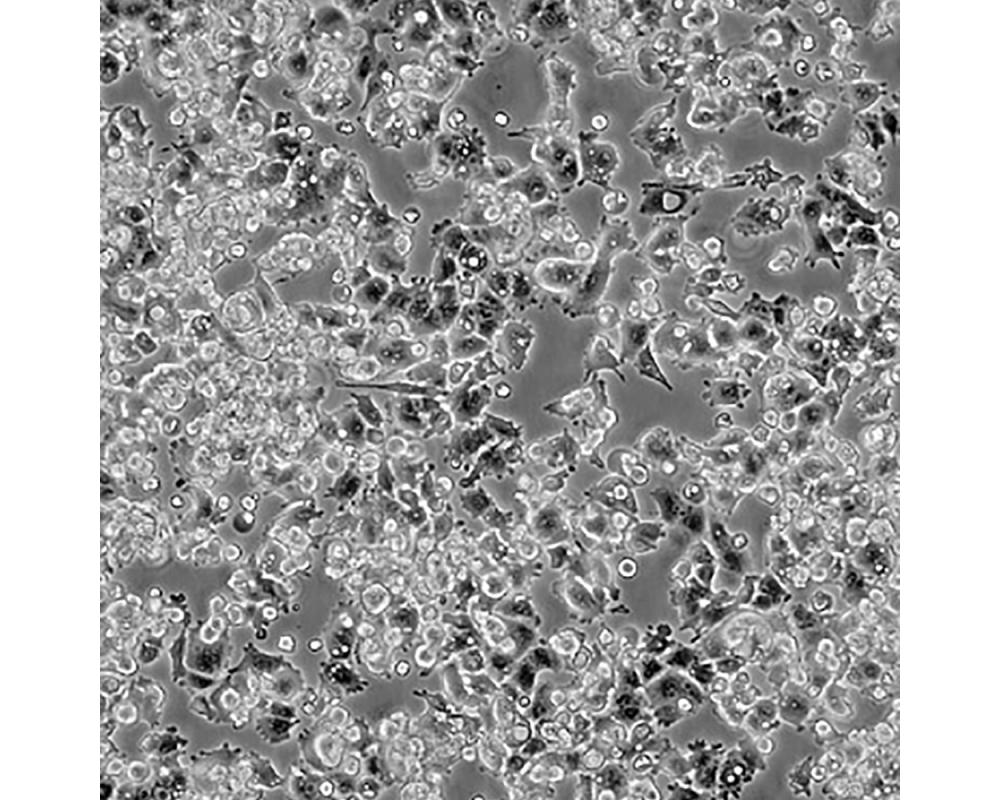

產(chǎn)品名稱 A-427

中文名稱 人肺腺癌細胞

組織來源 肺腺癌;男性

生長特性 貼壁

培養(yǎng)基 1640,90%;FBS,10%;雙抗。

培養(yǎng)條件 Atmosphere: Air, 95%; CO2, 5%。Temperature: 37℃